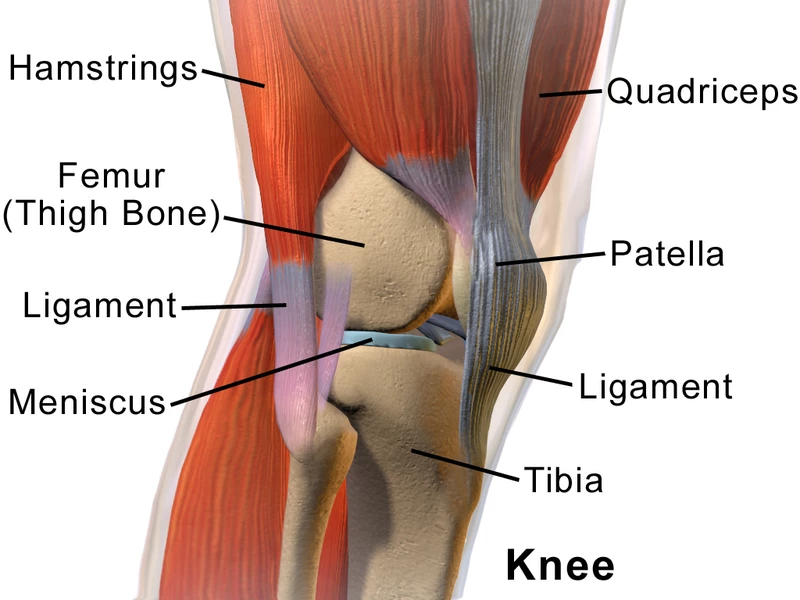

Degradation of the knee cartilage can be brought on by all sorts of causes – trauma, hereditary and developmental factors or even just plain wear and tear – but the result is the same. Without healthy cartilage cushioning the point where the femur sits on top of the tibia, those two bones grind away at each other with the full weight of the body behind them, causing painful and incapacitating damage over time.